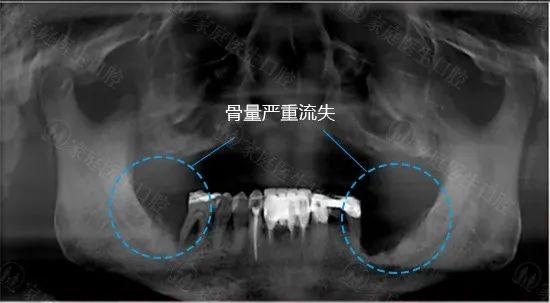

01牙槽骨的健康情况

一般情况下老年人钙质流失严重,加上缺牙颗数多,牙槽骨更容易出现吸收萎缩的情况。

种植牙对于牙槽骨的高度和宽度有一定的要求,所以老年人在做种植牙之前要注意维护牙槽骨的健康。如果牙槽骨流失较多,可以通过植骨的方法进行修复。